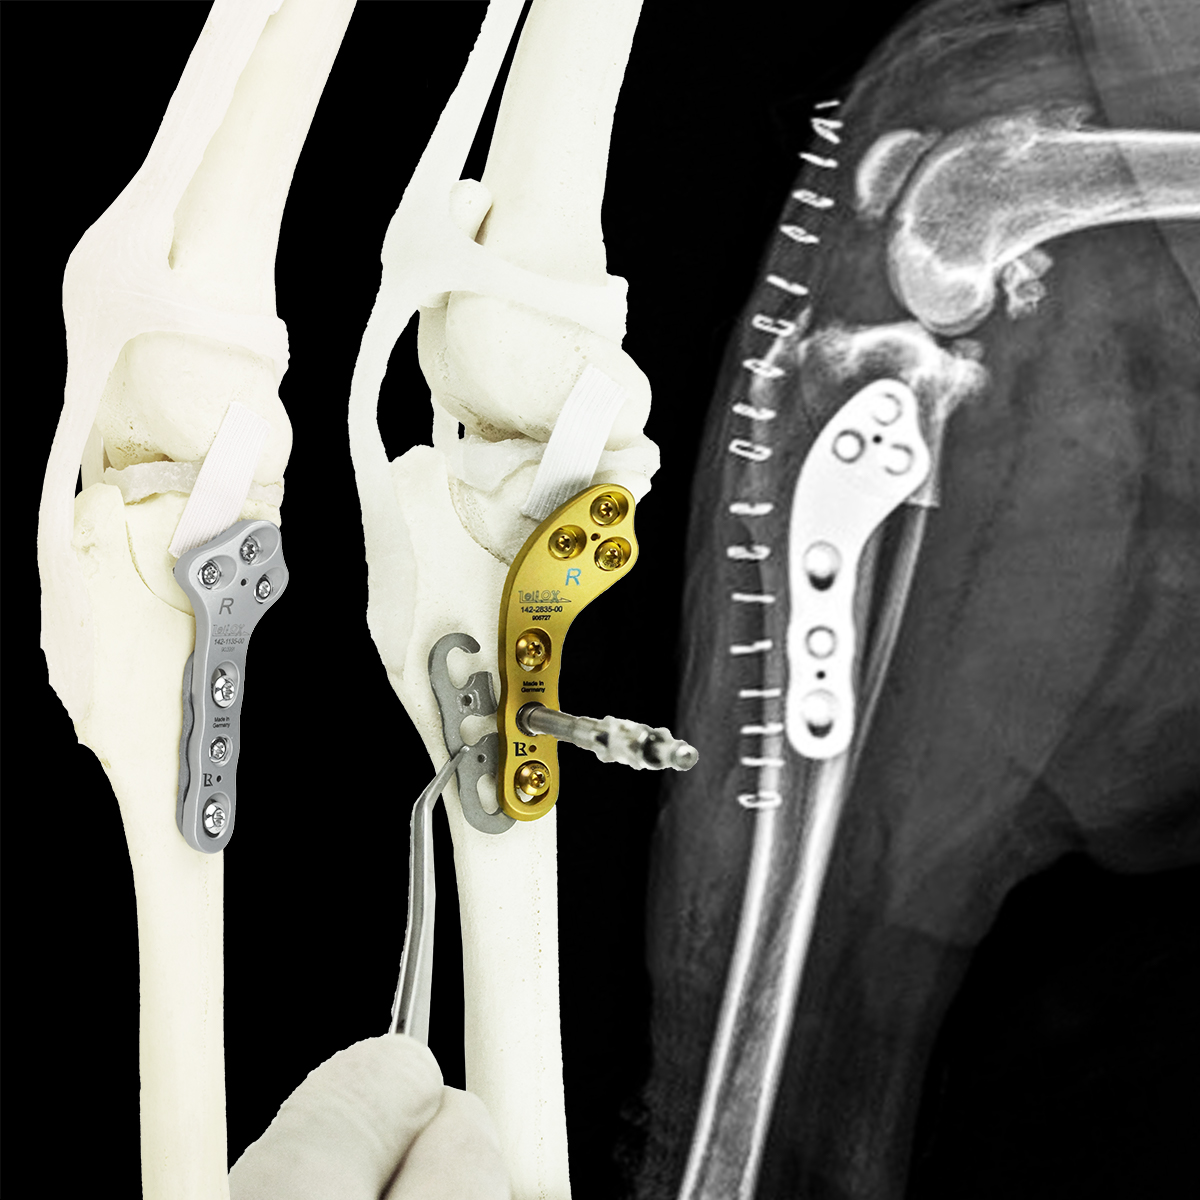

TTA RAPID®

Learn how to perform CCL Repair with TTA RAPID®

Dr. Yves Samoy shares with you his knowledge that he has gained since the beginning of TTA RAPID®. This online course is recorded with the same presentation materials used in the "live" wet-labs all around the globe. You may ask questions in the comments section of each chapter. Dr. Samoy will then receive an email with your question and follow-up with you that way.

This virtual course offers a long and detailed "real" surgery with live comments from Dr. Yves Samoy.

Tiny TTA RAPID®

Learn how to fix CCL Ruptures in Tiny Animals with the Tiny TTA RAPID® System

Dr. Hugo Schmökel shares with you all his knowledge about CCL Ruptures in Tiny Animals. It will be divided into a theoretical and a practical part. You may ask questions in the comments section of each chapter. Dr. Schmökel will then receive an email with your question.

The only difference between this online course and a wet-lab is the practical part. This course offers a long and detailed "real" surgery with the live comments from Dr. Hugo Schmökel. But you are required to practice on your own with cadavers.

Rapid Luxation

Learn how to fix Patella Luxation with the RAPID LUXATION System

Patella Luxations can be challenging, especially using previous techniques. Luckily, we have developed a seamless, simple technique for addressing both patella luxations and cruciate ligament ruptures.

Dr. Hugo Schmökel shares with you all his knowledge about Patellar Luxations. The course is divided into a theoretical and a practical part. Any questions may be asked in the comments section of each chapter, which will then be received and responded to by Dr. Schmökel.